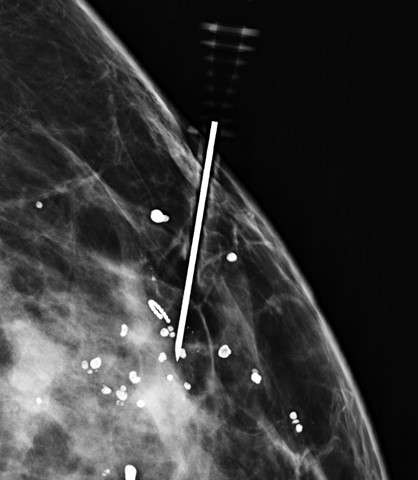

Technologist obtains orthogonal image of the breast (Figure 3).

Procedure Mammographically Guided Wire Localizations Figure 3

Figure 3: Spot mediolateral (ML) view of the needle in the same patient.